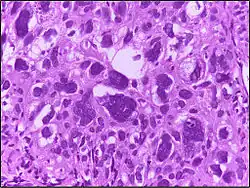

![]() | Tumor giant cell | Malignant neoplasm showing marked anaplasia. Note the marked nuclear pleomorphism, bizarre cells and tumor giant cells. | Category: Histopathology of giant cell tumors | Giant cell tumor |